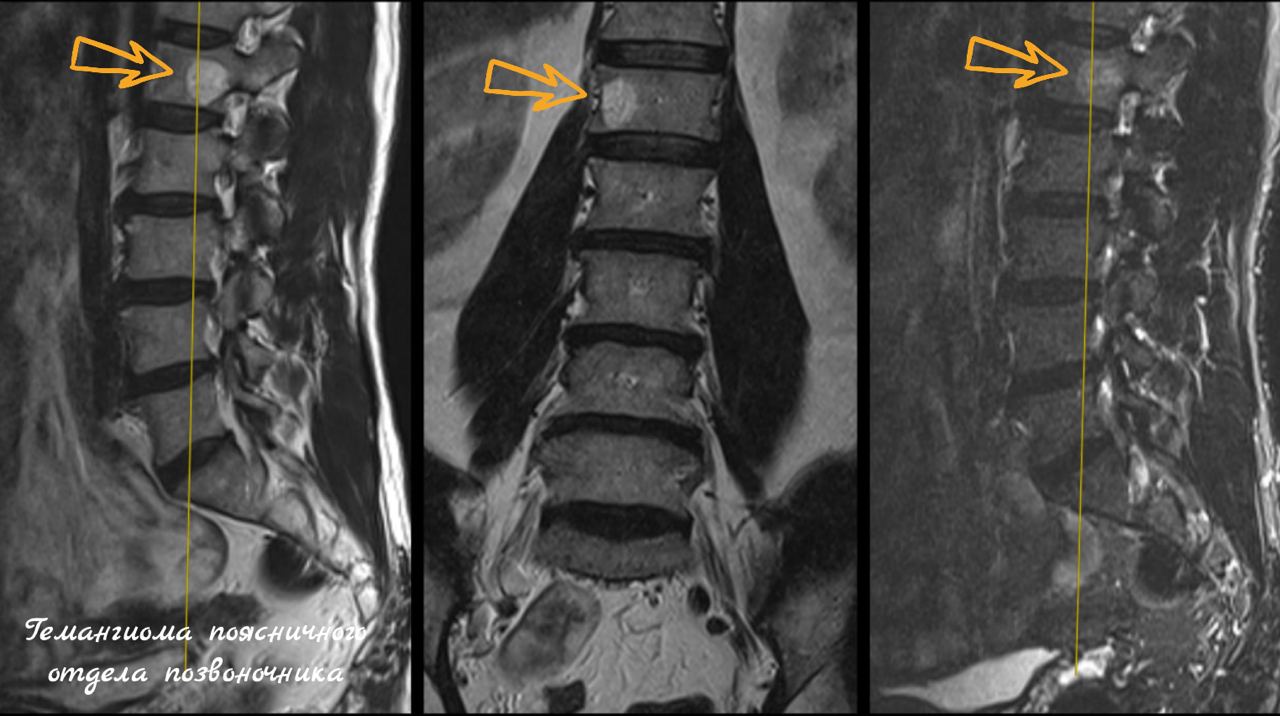

- Магнитно-резонансная томография (МРТ) — «золотой стандарт». Она безопасна (нет облучения) и идеально показывает саму гемангиому, её тип, а также сдавление спинного мозга и нервов.

- Компьютерная томография (КТ) — лучше всего показывает изменения в костной структуре позвонка, «клубничный» узор и возможное разрушение кости.

- В грудном и поясничном отделах позвоночника.

- Типичные (99% случаев): содержат много жира, стабильны, не растут. На снимках имеют характерный «клубничный» или «полосатый» рисунок. Не требуют лечения.

- Атипичные: содержат больше сосудов, менее жирные. Нуждаются в наблюдении, так как их сложнее отличить от других образований.